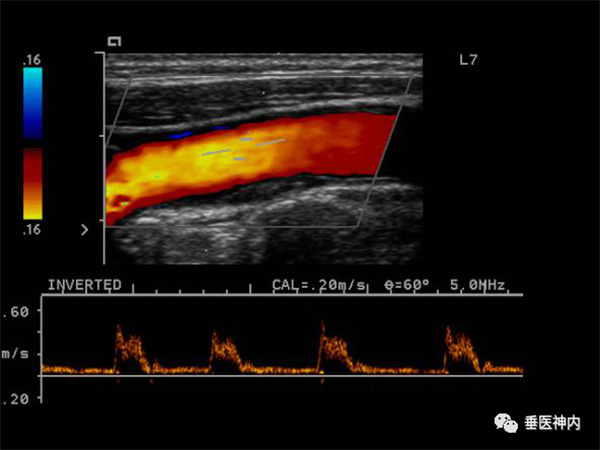

三、颈动脉彩超与经颅多普勒超声(TCD)

颈动脉超声是诊断、评估颈动脉壁病变的有效手段之一,可清晰显示血管内中膜是否增厚、有无斑块形成,斑块形成的部位、大小、性质以及是否有血管狭窄、狭窄程度、有无血管闭塞等。

经颅多普勒超声是检查颅内脑血管的方法。通过检测大脑主要供血动脉的血流动力学特征,判断是否存在血管狭窄或闭塞以及血流代偿情况。

此两种超声检查的优点是简便、无创、价格不高,各级医院均可开展;缺点是只能评价局部血管、受设备和操作人员技术水平限制检测结果可能存在差异性。常常用于体检或临床初筛检查,必要时需做进一步血管评估。